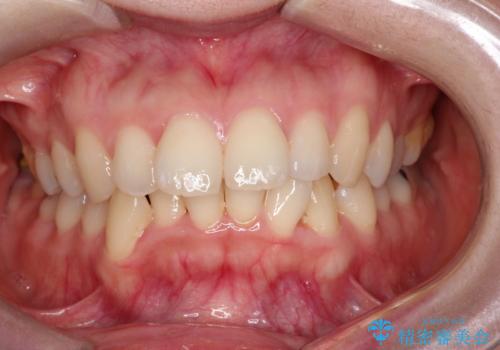

- 「歯のデコボコと前歯が出ているせいで口が閉じにくい」を主訴に来院された患者様です。

抜歯矯正により歯列のデコボコ(叢生)が改善し、前歯の突出も解消されたことで口元が下がり、すっきりとした印象となりました。

患者様にも大変ご満足いただけました。